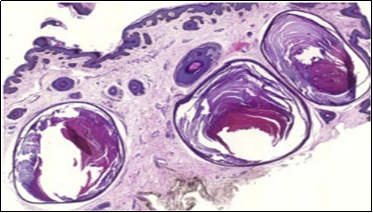

A cogent tissue specimen demonstrates typical features of comedones as follicular ostia distended and impacted with keratin. Significant histological manifestations are the occurrence of enlarged, grouped, distended follicular ostia demonstrating an absence of hair shafts along with impaction of laminated keratin. Base of the follicular invaginations may or may not delineate singular, rudimentary glandular structures. Miniature cysts, cystic invaginations and occasional enlarged cysts can be encountered. Cystic articulations are diverse and preponderantly layered by keratinizing, stratified squamous epithelium. Hyperkeratosis or epidermolytic hyperkeratosis and acanthosis of superimposed epidermis can concur although the lesion is devoid of parakeratosis or dyskeratosis5, 6.

Nevus comedonicus demonstrates immune reactivity to cytokeratin, simulating the expression of normal cutaneous surfaces. Generally encountered within the granular epidermal layer, immune reactivity for filaggrin is demonstrable within the entire epidermal thickness of closed comedones, a molecular which can be implicated in the genesis of nevus comedonicus6, 7. Electron microscopy demonstrates an enhanced quantification of Langerhans cells, numerous kerato-hyaline granules along with an abundance of tonofilaments within upper portion of stratum spinosum. Incompletely differentiated arrector pili muscles are impacted with intracellular glycogen particles6, 7. Figure 1, Figure 2, Figure 3, Figure 4, Figure 5, Figure 6, Figure 7, Figure 8, Figure 9, Figure 10.

Figure 9.Nevus comedonicus exemplifying a dilated, plugged follicular ostium, keratinous flakes and a layer of stratified squamous epithelium17.

Figure 10.Nevus comedonicus depicting an impacted, distended follicular ostium, keratinous aggregation and a superimposed, acanthotic, hyperkeratotic, stratified squamous epithelium17.